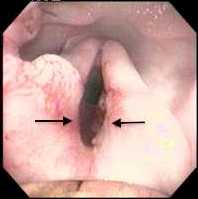

Cambridge Boas Research Group What Are Laryngeal Saccules The Larynx Voice Box Is A Cartilaginous Structure At The Back Of The Throat It Is The Gatekeeper Of The Lower Airway

Everted Laryngeal Saccules Southern Animal Health